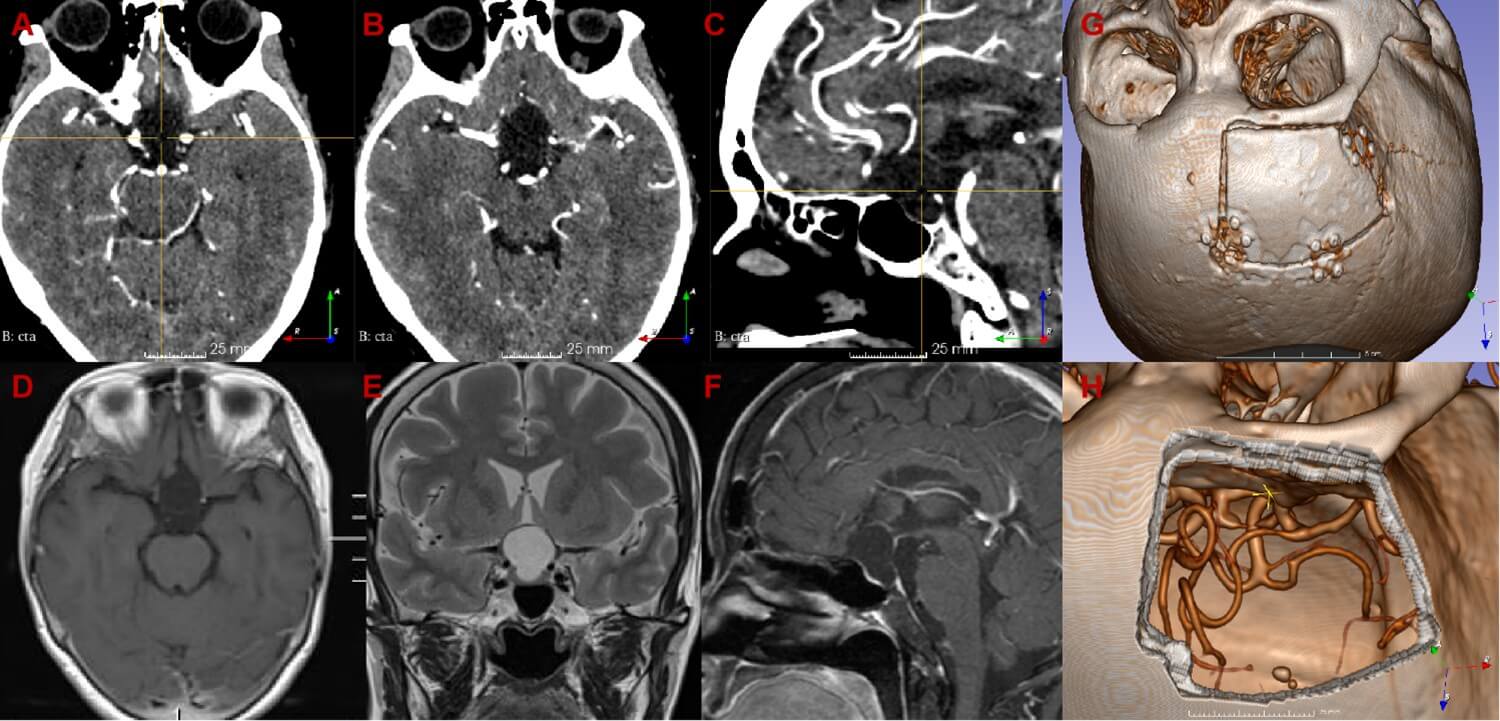

4. Imaging Findings (Figure 1)

CT revealed a hypodense lesion without calcification. CTA demonstrated the lesion's close proximity to the Circle of Willis. MRI identified an intrasellar-suprasellar cystic lesion measuring approximately 2.2×1.8×1.7 cm3, showing no significant enhancement. The pituitary gland was displaced anteriorly, with poor visualization of the pituitary stalk.

6. Operative Procedure (Figure 2-4 & Video 1)

A right subfrontal approach was performed. A frontotemporal skin flap and subfrontal craniotomy were created, followed by flattening of the anterior skull base. The dura was carefully reflected toward the frontal base, followed by sequential opening of the optic nerve cistern, carotid cistern, and sylvian cistern to access the tension triangle of anterior cranial base, allowing controlled cerebrospinal fluid (CSF) release. The arachnoid membranes around the optic nerves and chiasm were dissected. Upon exploration of the first interspace (the space between the bilateral optic nerves), a translucent, cystic lesion was identified with fine vascular networks on its surface. The cyst displaced the optic nerves and internal carotid arteries laterally, partially occupied the prepontine cistern posteriorly, compressed the optic chiasm superiorly, and extended into the sella inferiorly. The arachnoid adhesions between the cyst and the surrounding structures (optic nerves, chiasm, and internal carotid arteries) were meticulously dissected. No distinct pituitary stalk was initially visualized. A fenestration was made in the avascular region of the cyst’s anterior wall, releasing clear, colorless fluid and reducing the cyst’s tension. Upon decompression, a dark-red pituitary stalk became visible within the cyst wall. Further arachnoid dissection around the stalk was performed, followed by fenestration and partial resection of the cyst’s posterior avascular wall, exposing the proximal basilar artery in the prepontine cistern. Intrasellar exploration confirmed the pituitary gland’s anterior position. The pituitary stalk and hypothalamic structures were preserved intact, with no injury to the optic nerves or surrounding vessels. The procedure was concluded with watertight dural closure, obliteration of the frontal sinus, repositioning of the bone flap, and multilayer scalp suturing.

7. Clinical Outcomes (Figure 5)

The patient recovered uneventfully without postoperative complications such as fever or diabetes insipidus. The scalp incision healed well. Follow-up CT showed no surgical site hemorrhage, while MRI demonstrated complete resolution of the sellar cyst with preserved pituitary gland and stalk anatomy. Pathological examination confirmed the diagnosis of a benign cyst.